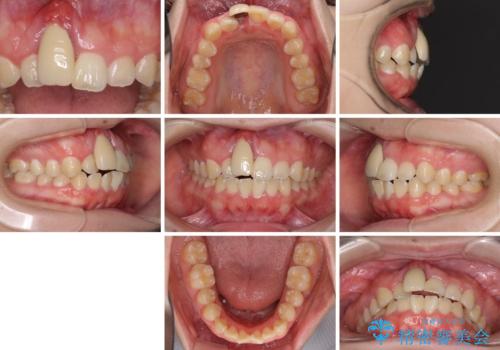

- 中学生の頃にぶつけた前歯に不格好なクラウンが装着されており、出っ歯な印象になっていることを気にして来院された患者様です。

ぶつけてしまった歯は保存が困難な状況であったので抜歯をし、ワイヤー矯正により歯列を整えつつ前歯の突出感を解消することとしました。

矯正治療後にはインプラント補綴治療を行うこととしました。

前歯の補綴治療はインプラントかブリッジかで悩んでいました。

周りの歯にむし歯がないため、インプラントがお勧めとなりますが、事故による骨欠損が大きく、歯肉ラインを整えるのが困難という問題がありました。